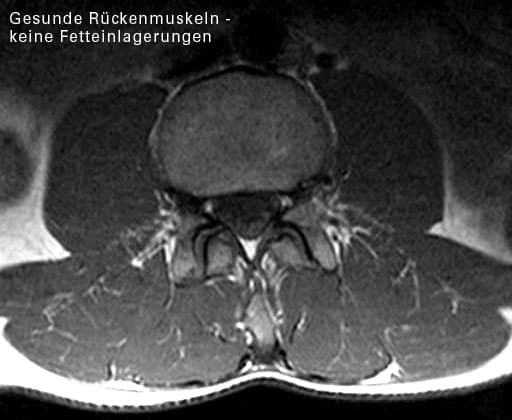

Abbildung eines degenerierten Rückenmuskels